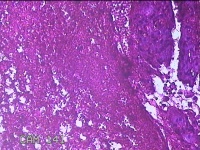

右卵巢黄体囊肿

性别

女

年龄

41岁

临床诊断

右卵巢黄体囊肿破裂

一般病史

下腹痛3小时。

标本名称

大体所见

灰白暗红色囊性肿物2x0.8x0.7cm一个,表面糜烂,切开肿物,内见大量凝血块,囊壁厚约0.1cm。

图1